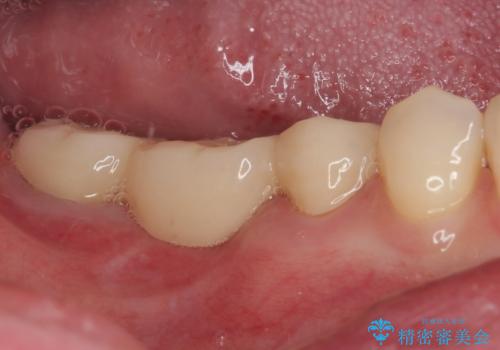

破折して抜歯が必要となった奥歯 オールセラミックブリッジ治療

根管治療を行った奥歯をブリッジの支台歯としているため、咬合力による負担を軽減するために、就寝時にマウスピースを装着するように指導しています。